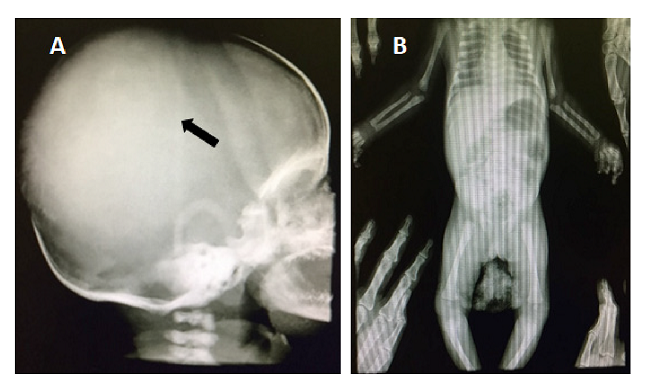

El Servicio de Hematooncología descartó el diagnóstico de linfoma dado que no es característico en el rango de edad del paciente, y los síntomas y el curso clínico concordaban más con histiocitosis, por lo cual se hicieron pruebas de inmunohistoquímica y se obtuvieron radiografías de tórax, cráneo y huesos largos, en las cuales se observó incremento del volumen de los huesos de la bóveda craneana y la desproporción craneofacial (figura 4). Dado el resultado de patología, se inició la quimioterapia prefase con prednisona y ciclofosfamida.

En los niños, la histiocitosis de células de Langerhans puede afectar cualquier hueso del cuerpo, sobre todo el cráneo (40 %), el fémur, las costillas, las vértebras y el húmero 11. En el caso en estudio, hubo aumento de volumen de los huesos de la bóveda craneana y desproporción craneofacial, pero no hubo afectación de huesos largos u otra estructura ósea.

En conclusión, la histiocitosis de células de Langerhans es una enfermedad rara de las células mieloides que puede afectar a cualquier grupo de edad y abarca un amplio espectro de manifestaciones locales y sistémicas, dependiendo del estadio y los órganos comprometidos. Su causa es desconocida y se caracteriza por proliferación de las células de Langerhans. Tiene diferentes manifestaciones radiológicas y, muchas veces, el primer estudio diagnóstico corresponde a la radiografía simple de la zona afectada, cuyos hallazgos pueden ser difíciles de interpretar y requieren confirmación mediante los análisis histopatológicos. Por ello, la enfermedad representa un desafío y es importante sensibilizar al personal médico sobre la necesidad de profundizar en su conocimiento para un diagnóstico y manejo oportunos.